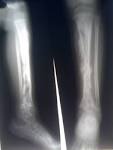

10 жастағы Дамира есімді қыз облыстық балалар ауруханасына былтырғы жылдың қазан айында жатқызылыпты. Науқастың оң аяғындағы бақайлары дұрыс жетілмеген. Бірақ дәрігерлер неге екені белгісіз науқастың сол аяғын емдеуді қажет деп шешіпті. Ал анасы операция қате жасалған деп отыр.

Ал дәрігерлердің айтуынша, қыздың екі аяғы да ауырады. Сондықтан ең алдымен сол аяғына ота жасау қажет деп шешіпті. Бас дәрігердің айтуынша, операцияны жүргізген хирург ата-анасына ескертіп, ақылдасқан.

Дамира оңалтудан соң Ана мен бала ғылыми орталығына жіберілді. Ол жерде оның диагнозы расталды. Яғни, дәрігерлер тарапынан қателік болмаған.